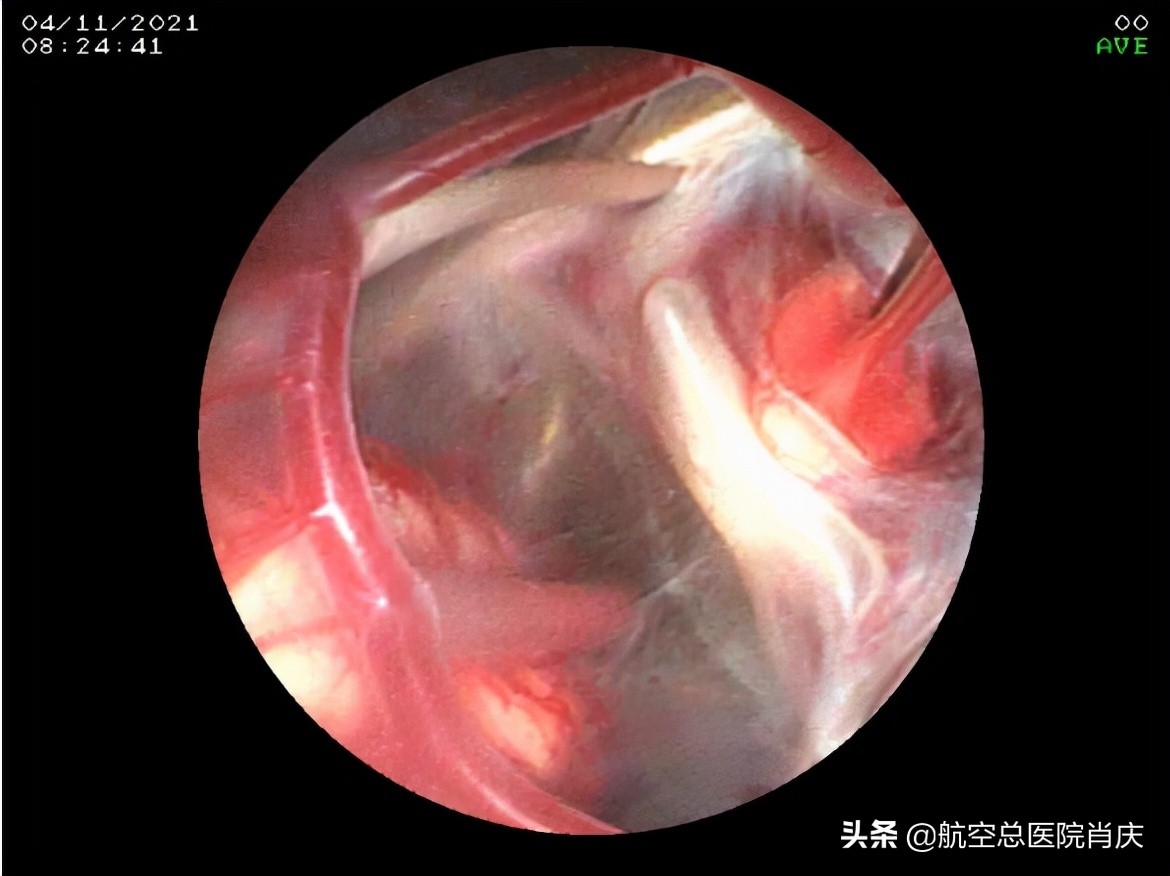

(内镜下所见鞍上池囊肿)

(鞍上池囊肿顶壁造瘘后经瘘口所见囊肿底壁及颅底动脉环)